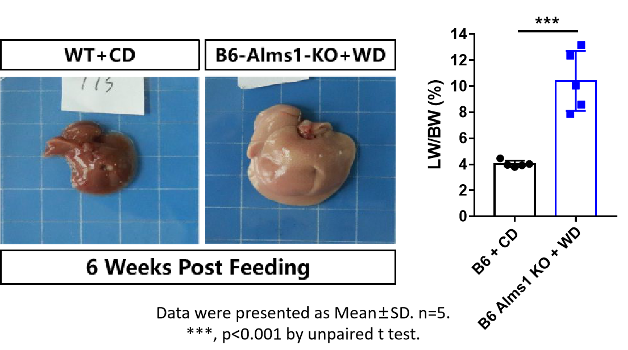

图片2.png

Figure 2. After 6 weeks of feeding, the B6-Alms1-del MASH mice exhibited a severe fatty liver phenotype. Data are presented as Mean±SD, n=5. ***, P<0.0001 by unpaired t test.